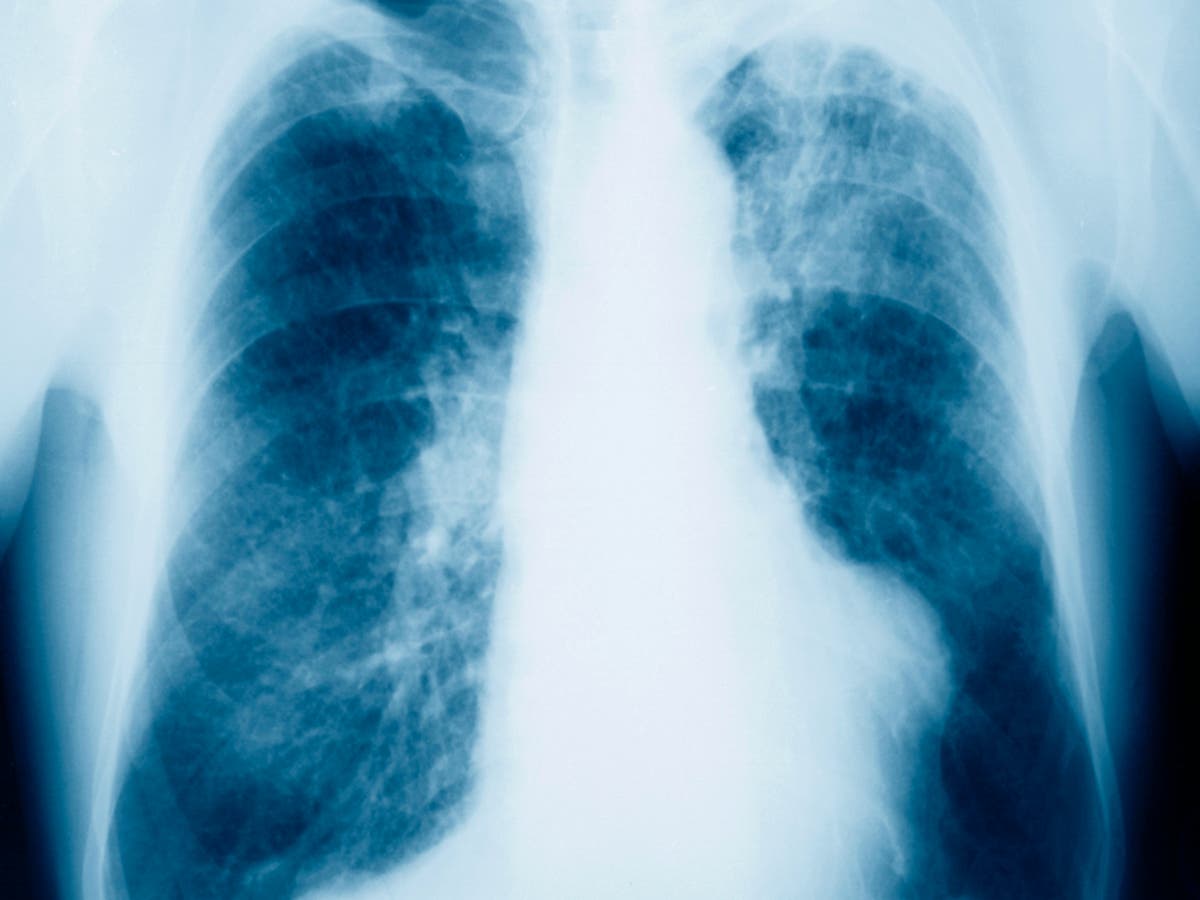

England Mother of Two Dies from Mesothelioma Tied to Childhood Asbestos Exposure

Elaine Ellery, a mother of two in Norfolk, England, died at 67 from mesothelioma. A Norfolk Coroner’s Court ruled her cancer was caused by asbestos exposure she endured as a child from her father’s work clothes and factory environment, including hugs and helping wash his overalls; her father died earlier from an asbestos-related industrial disease.